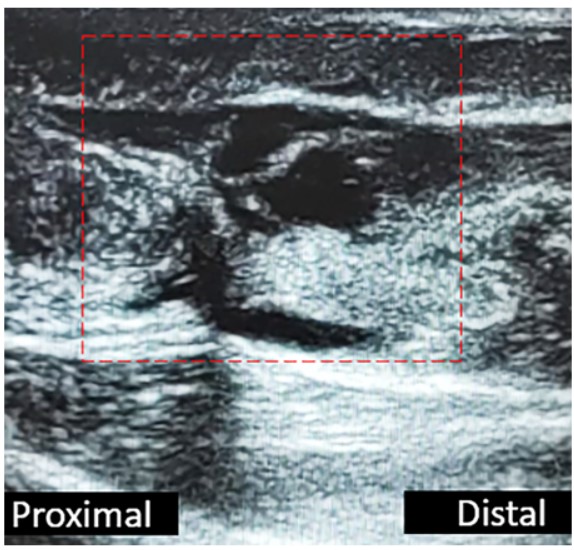

Se identifico el intervalo de la lesión en el tendón de Aquiles (Figura 2) y la trayectoria del nervio sural y su vena satélite (safena menor) mediante ecografía. Para identificar la vena fue de utilidad realizar compresión sobre los tejidos blandos y ver su colapso (Figura 3) (Figura 4).

Figura 2. Ecografía: visión longitudinal del tendón de Aquiles. Se visualiza solución de continuidad.